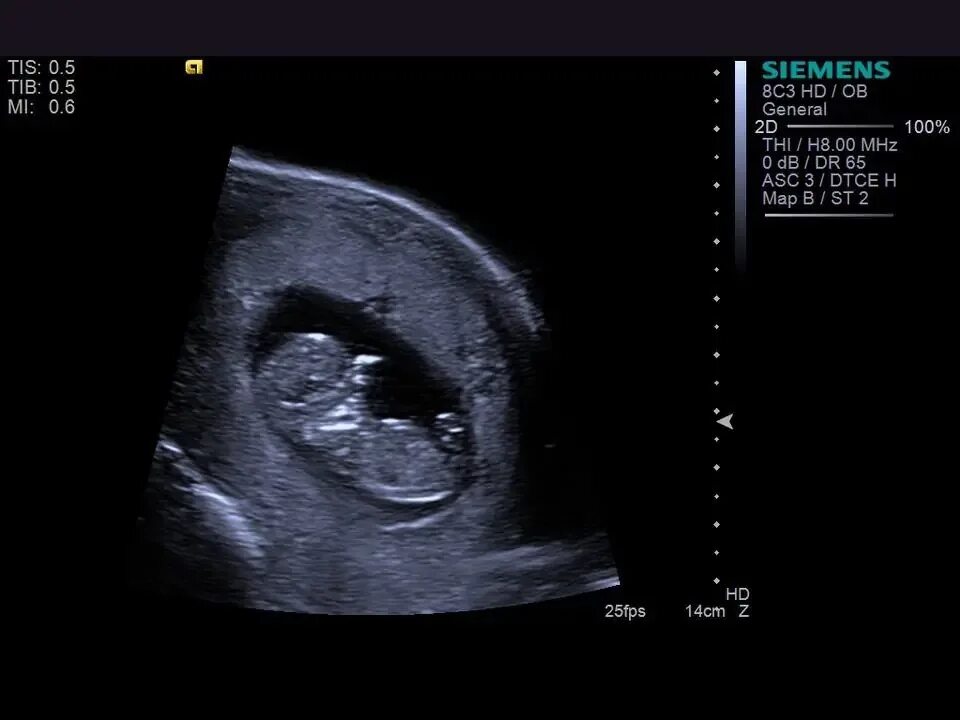

10 недель какие ощущения